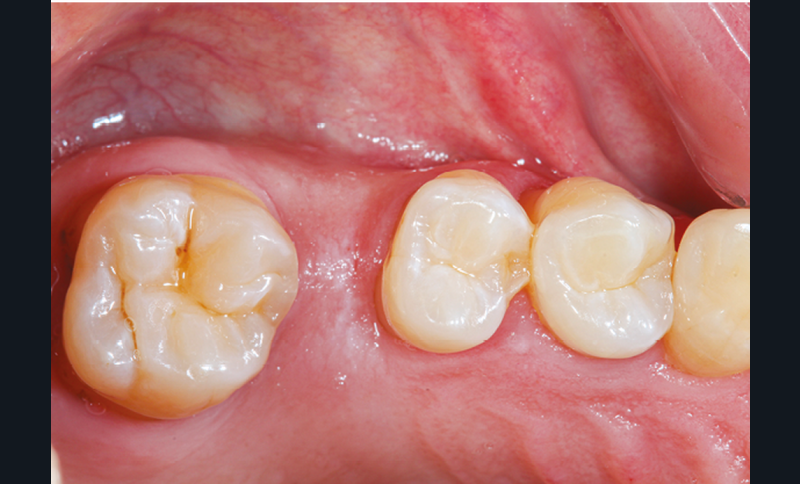

Des conséquences sur l’arcade antagoniste s’ajoutent à toutes les perturbations de l’arcade concernée. La dent antagoniste à l’édentement n’est plus calée et peut par conséquent s’égresser. Cette égression modifie les points de contact et les espaces interdentaires, pouvant conduire à des tassements alimentaires et des caries secondaires [18, 19].